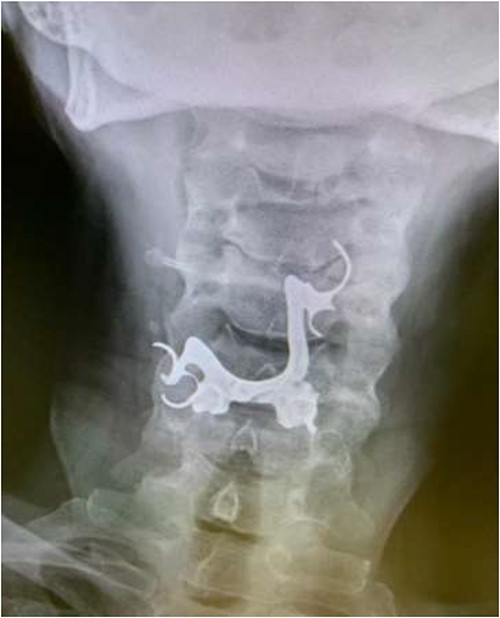

The first case is of a 7-year-old child presenting with a history of barbed wire inhalation. X-ray imaging of his neck and chest showed a radio-opaque object visible in the upper airway with sharp edges (Figs 1 and 2). Due to the position of the foreign body, endotracheal intubation was not feasible. A trial of apnoeic oxygenation using high-flow nasal oxygenation was used as an alternative, and this allowed for an unobstructed view of the larynx, facilitating the safe removal of the foreign body (Fig. 3).

Lateral neck X-ray showing a radio-opaque object with sharp edges visible.